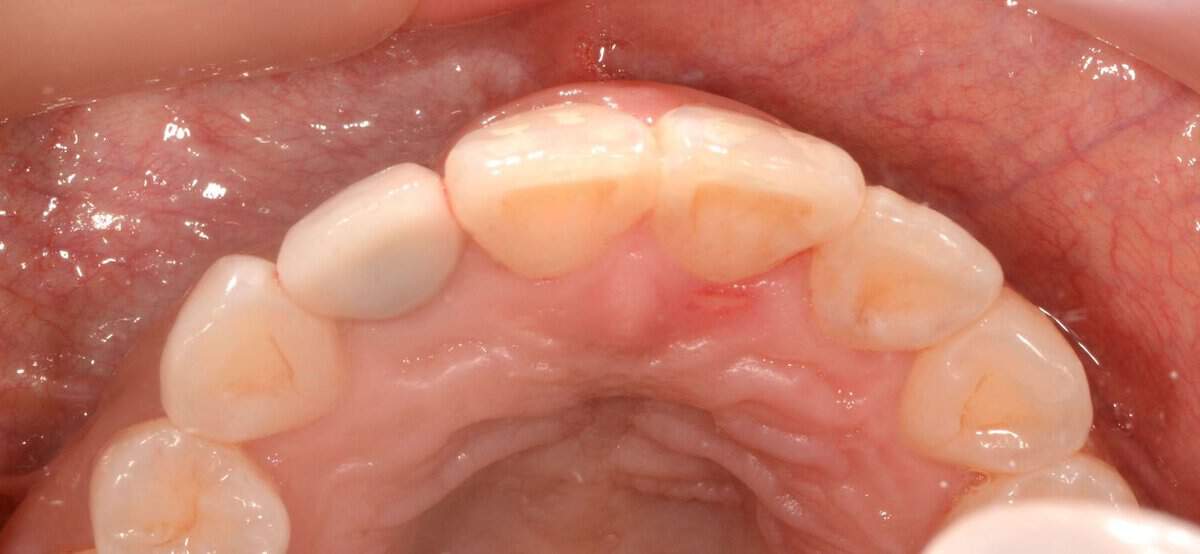

Locator abutments of mandibular overdenture, burried under the swollen and inflamed oral mucosa. Resolution of the inflammation in such cases is very challenging, but unless some surgical adjustment of the peri-implant tissues takes place the problem can be recurrent.

Baloon-style swelling of the tissues around locator abutment of mandibular overdenture, combined with Peri-implantitis. Adjustment of the soft tissues in combination with teh peri-implantitis surgery is essential in such cases to minimise the risk of recurrence.